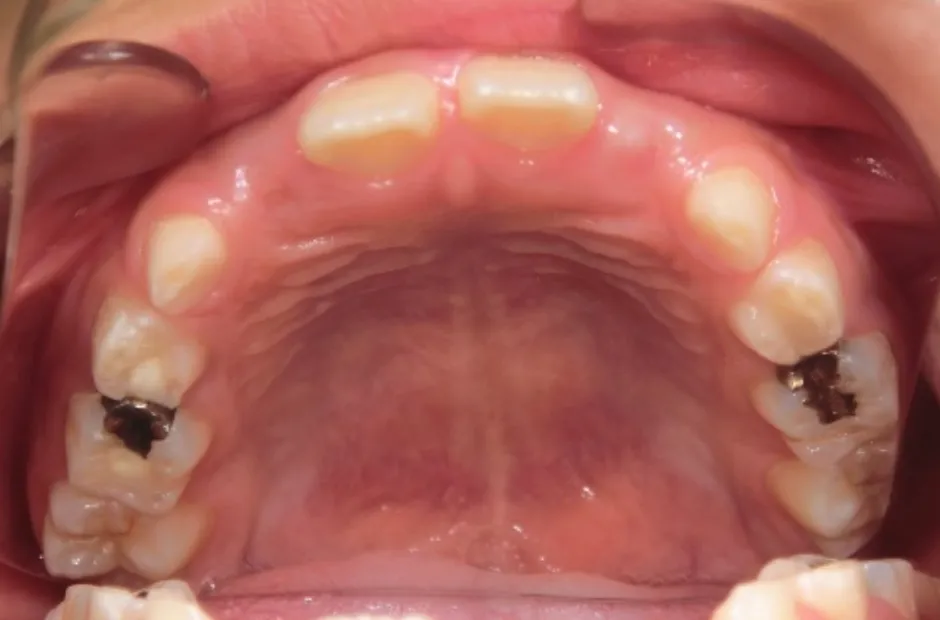

叢生

| 診断名・主訴 | 叢生 |

|---|---|

| 年齢・性別 | 10歳・女性 |

| 治療期間・回数 | 2年半 |

| 治療に用いた主な装置 | 拡大床装置 |

| 抜歯部位 | なし |

| 治療費 | 30万円(税抜) |

| リスク・副作用 | 装置による違和感・疼痛・歯肉退縮・歯根吸収・虫歯のリスクなど |

治療前

治療中

治療後